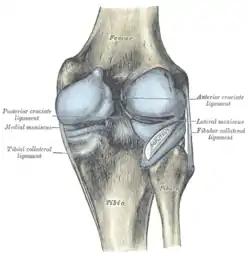

The medial collateral ligament, posterior cruciate ligament, anterior cruciate ligament, and lateral collateral ligament are the four primary ligaments of the knee. The medial and lateral collateral ligaments primarily provide support to varus and valgus forces whereas the anterior and posterior cruciate ligaments prevent anterior and posterior translation of the tibia on the femur.[2]

The classic O'Donoghue triad is characterized by an injury to three knee structures (in order):

- the anterior cruciate ligament

- the medial meniscus (however, lateral meniscus[1] injuries are more commonly seen among athletes, leading to the definition of the O'Donoghue triad most commonly used today.) [3][4][5]

- the medial collateral ligament (or "tibial collateral ligament")

The anterior cruciate ligament is one of the four crucial ligaments in the knee. It originates from the lateral condyle of the femur and goes to the intercondyloid eminence of the tibia. Its function is to provide stability in the knee and minimize stress across the knee joint. It also restrains excessive forward movement in the leg and limits rotational movements in the knee.

Meniscus

The medial meniscus is a C-wedge shaped piece of cartilage that acts as a"shock absorber" between the femur and the tibia. Each knee has two menisci, one at the outer edge and one at the inner edge of the knee. The menisci are tough and rubber-like to help cushion the joint and help keep it stable.

The lateral meniscus is also known as the external semilunar fibrocartilage. It is a fibrocartilage band on the lateral side of the knee joint and can easily be injured with torsional stress or direct force.